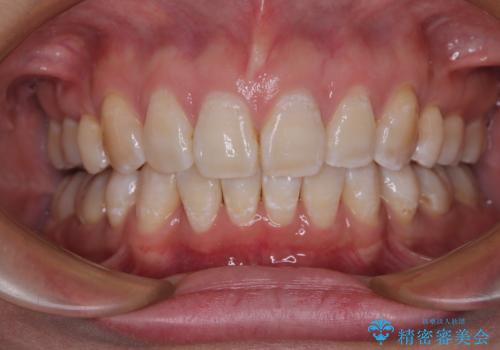

- 上顎歯列の出っ歯を気にして来院された患者様です。

骨格的に上顎歯列が前方位にあり、口元の突出感が顕著な状態で、上下左右の第一小臼歯4本を抜歯して、ワイヤー装置での抜歯矯正を行うこととしました。

ご本人がびっくりするくらい劇的に口元の突出感が改善され、大変満足のいく仕上がりとなりました。